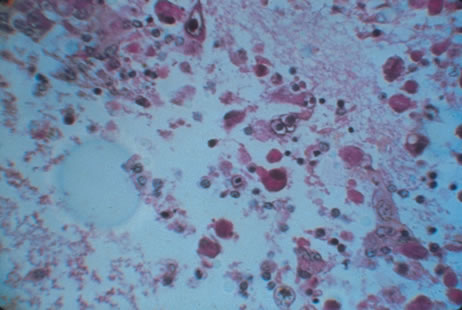

Any cell type may be infected, appearing larger than normal (cytomegalic) and demonstrating eosinophilic intranuclear “owl's eye” and smaller intracytoplasmic viral inclusion bodies, which are better seen with Giemsa or Papanicolaou's stains (Fig. 8). Histologic examination of tissue specimens, including bronchoalveolar lavage fluid and urine, may be useful for diagnosis.